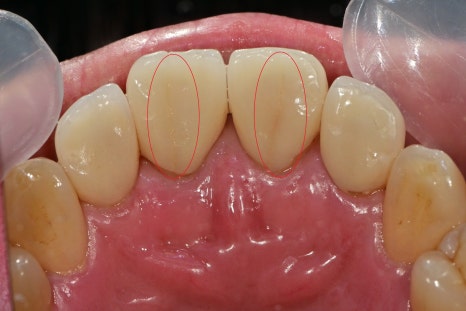

정면에서 봤을 때 2개의 보철물이 파절되었고 치아 사이가 살짝 벌어져있었습니다.

이런 경우에는 최소한 대칭적으로 파절된 2개의 보철물을 재제작하는것이 가장 좋습니다만

환자분께서는 정면에서는 하나의 치아만 파절선이 보여 그것만 교체를 원하셨습니다.

이럴 경우 치아가 빈 공간을 채워주며 모양이 비대칭적으로 형성된다는 한계는 있습니다

파절된 라미네이트같은 크라운을 제거한 사진입니다

사진과 같이 치축이 틀어져있는 치아를 보철을 이용해 고르게 만든 경우 같습니다

이 상태로 그대로 재보철시에는 보철물의 두께가 너무 얇아질 수 있기 때문에

보철물의 강도를 확보할 수 있는 선에서 치아를 만들었습니다